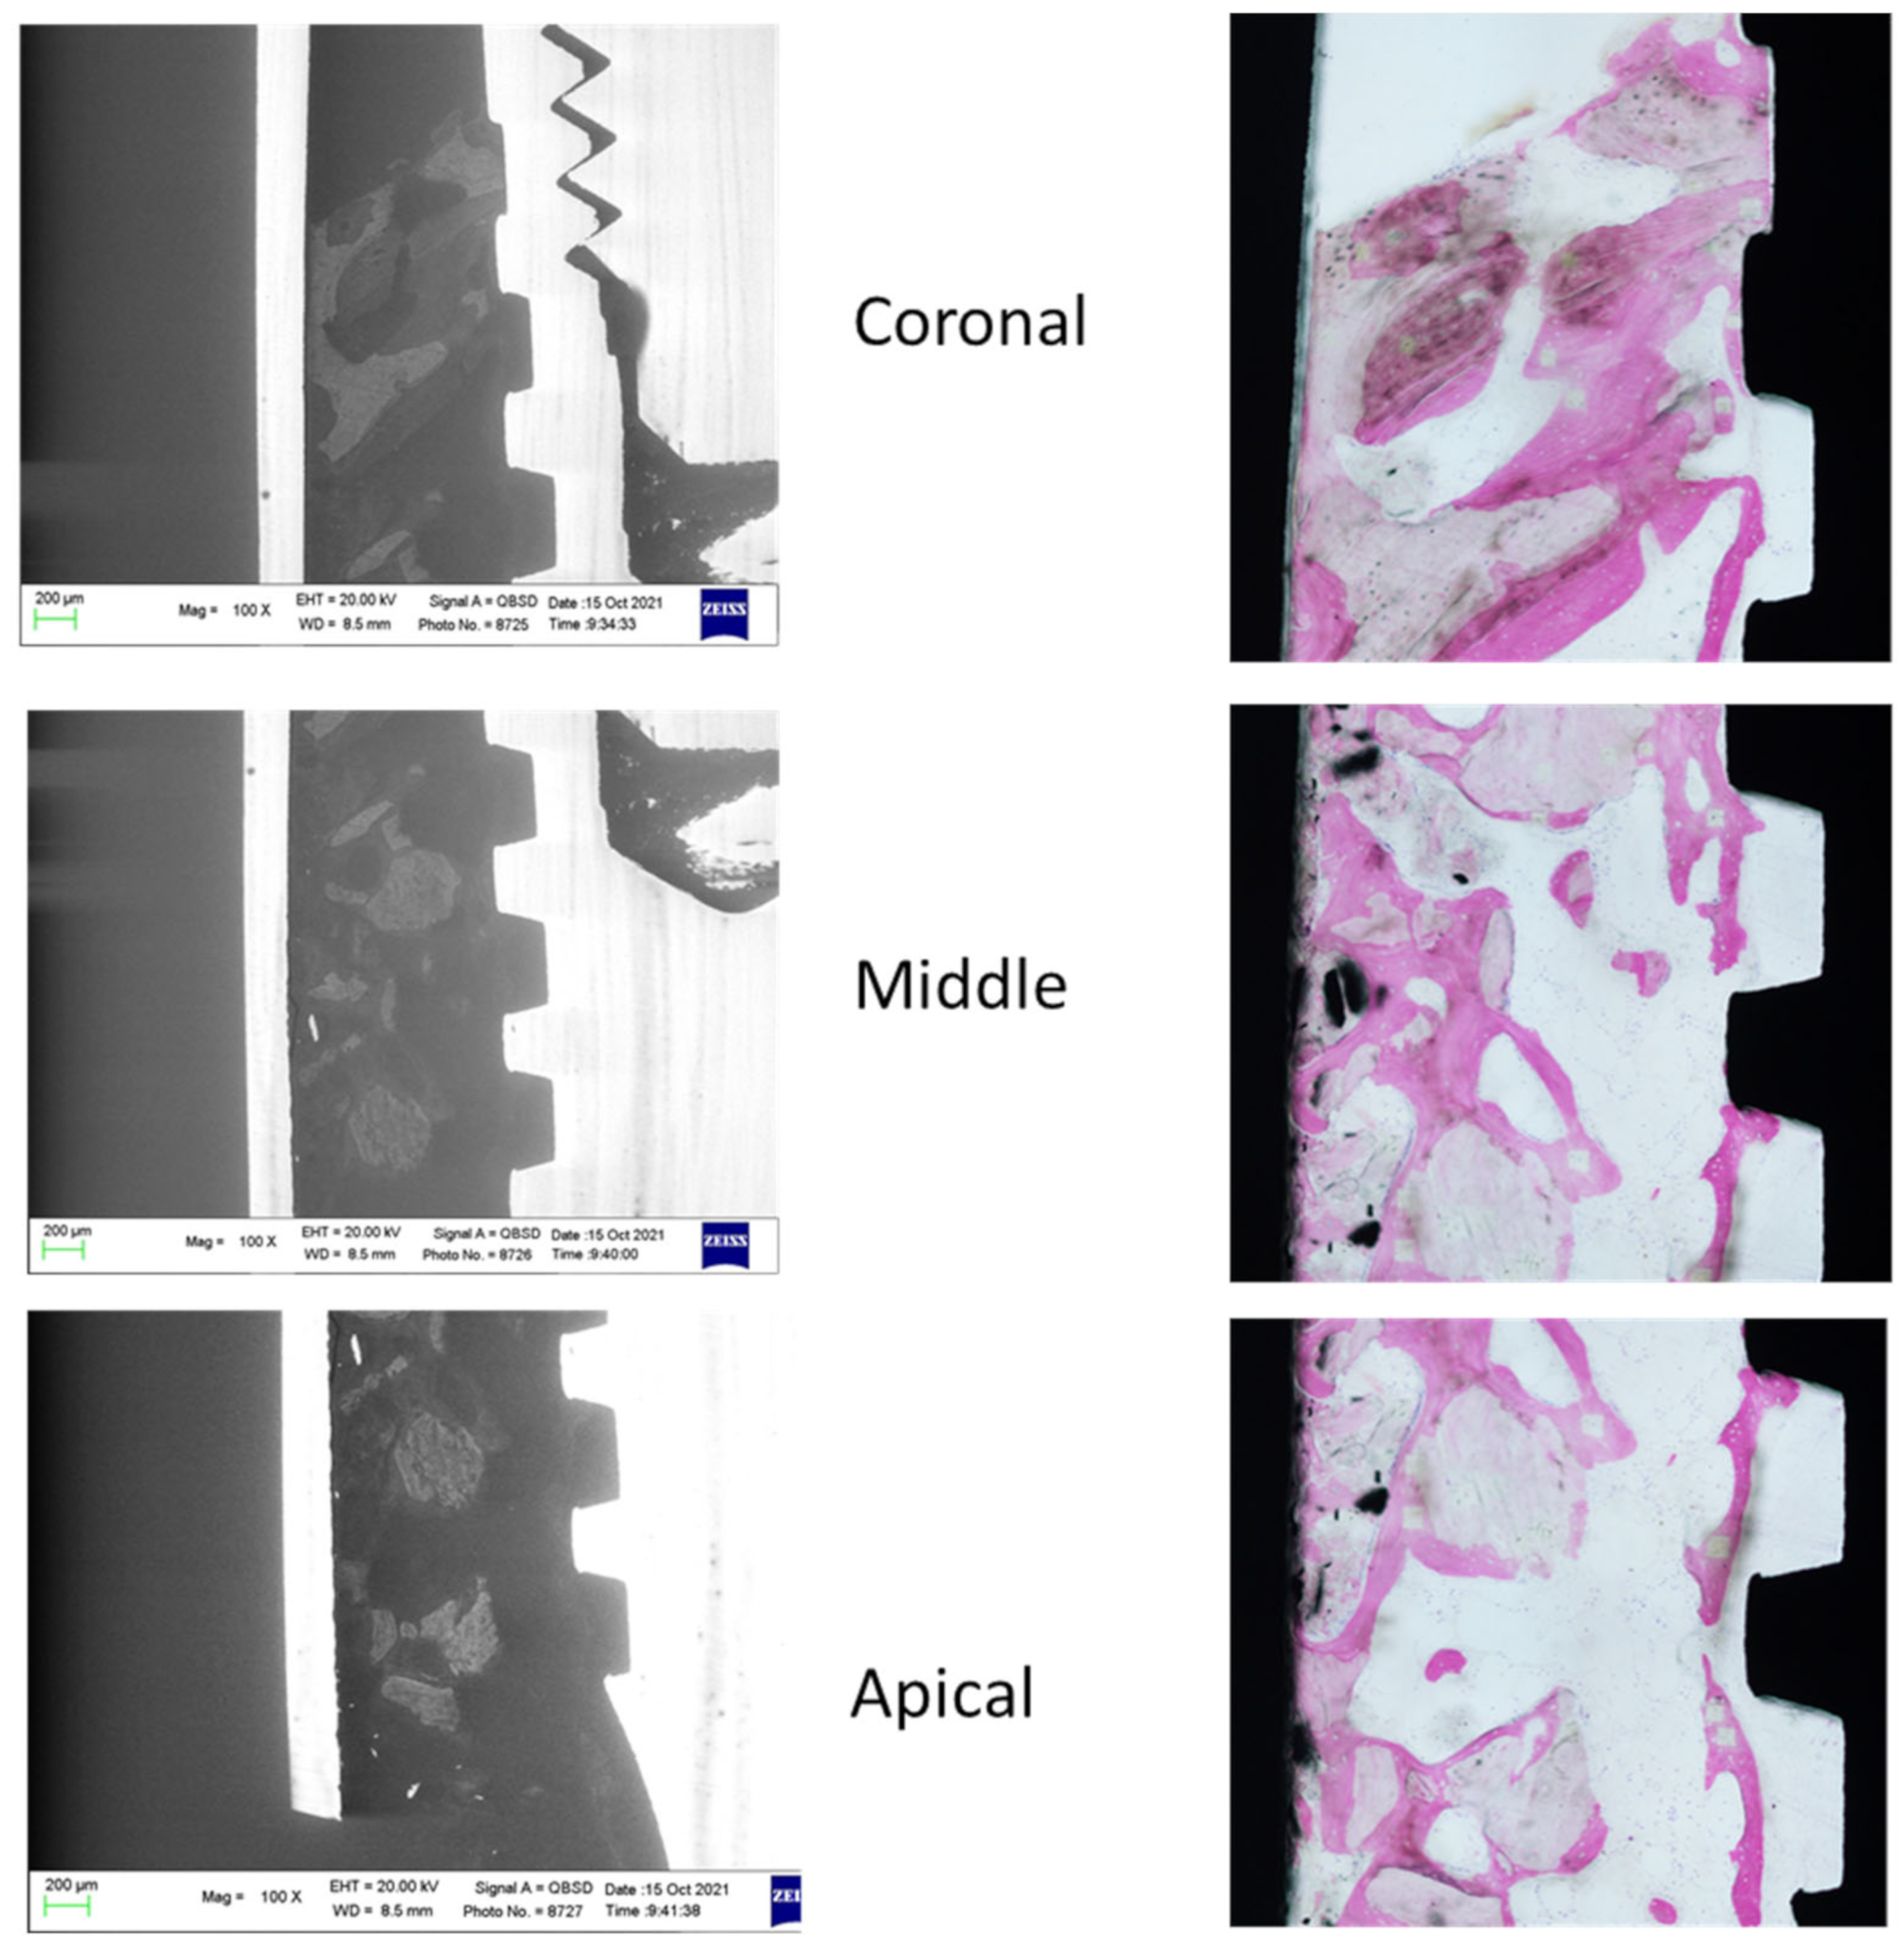

The ESEM-EDX analysis at the coronal, middle and apical ROI of two specimens included in the study is schematized in Figure 3 and Figure 4.

Figure 3. ESEM and OM images were obtained to identify bone tissue and bone grafts around the implant. Original magnification 100×.